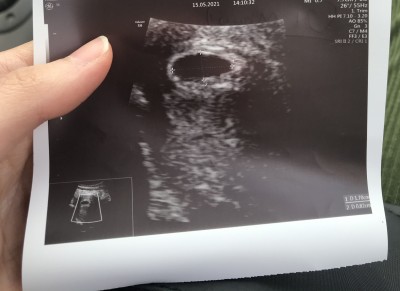

4 haftalık hamileyim kesem oluşmuş çok şükür boyutu normal mi sizce sizin nasıldı

Banada 1 hafta önce 4 haftalık dedi ama minicikti benim kese bu çok büyük geldi kaç mlim dedi doktor